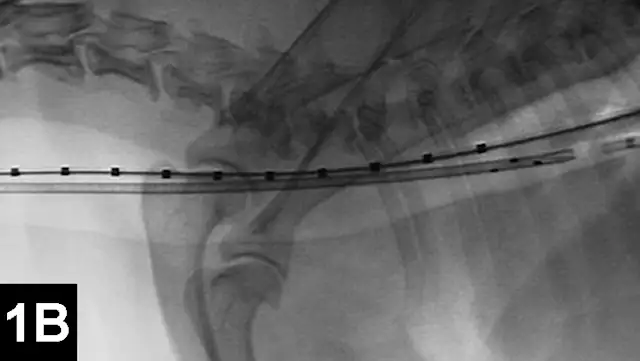

Clinical improvement can be achieved in 75% to 90% of animals treated with self-expanding metallic stents (Figure 1), an IR procedure.4 Immediate adverse events were mostly minor; however, a perioperative mortality rate of about 10% was reported. Longer-term adverse events included shortening of the stent, fracturing of the stent, progressive tracheal collapse, and excessive granulation tissue.

Figure 1A: Serial lateral fluoroscopic images of a dog with tracheal collapse.

A positive pressure ventilation demonstrates maximal dilation of the trachea. A marker catheter in the esophagus is used to account for radiographic magnification.